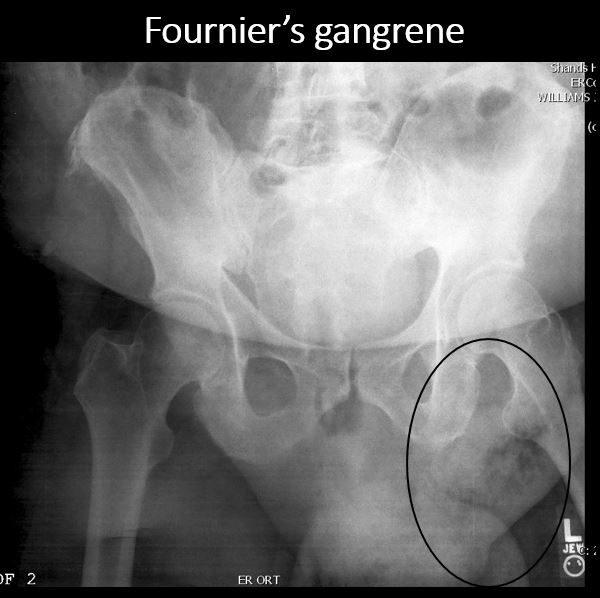

There is air or a foreign body in the extra- abdominal soft tissues of the abdomen, pelvis, or perineum. [Yes/No]